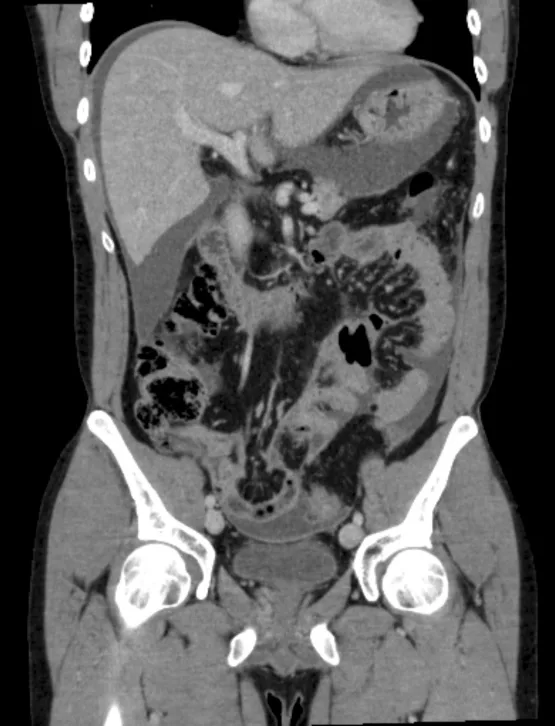

Même si le gradient sérum-ascite est bas, il s’agit dans la majorité des cas d’une ascite riche en protéines > 25 g/L. En cas d’ascite maligne, la physiopathologie de l’ascite est multifactorielle avec une augmentation de la perméabilité vasculaire et une obstruction du drainage lymphatique [7]. Cette augmentation de la perméabilité capillaire est favorisée par certaines cytokines comme le VEGF. Les cancers les plus fréquemment observés sont gynécologiques et en particulier ovarien mais également colorectal ou pancréatique [10]. À la différence des cancers solides, les ascites lymphomateuses sont plus rares. Une tumeur primitive péritonéale comme le mésothéliome est exceptionnelle avec une rentabilité diagnostique de la ponction d’ascite qui est moins bonne (< 40 %) que celle des carcinoses péritonéales sur cancer solide. Le scanner oriente le diagnostic (Fig. 1). L’augmentation de la mésothéline dans le liquide d’ascite a une sensibilité de 67 % et ne remplace pas l’analyse anatomopathologique. En cas de suspicion de mésothéliome, il faut avoir recours à la chirurgie cœlioscopique pour réaliser des biopsies péritonéales permettant un diagnostic de certitude [11]. La possibilité d’une exceptionnelle maladie gélatineuse du péritoine est évoquée devant une ascite récidivante riche en mucine avec une tumeur le plus souvent appendiculaire ou ovarienne [7].

Il s’agit le plus souvent d’une maladie vasculaire du foie avec une hypertension portale non cirrhotique [13]. De multiples maladies vasculaires du foie sont associées à une hypertension portale non liée à la cirrhose (Tableau III). En effet chez le patient cirrhotique, le gradient porto-sus hépatique > 5 mm/Hg est lié à l’augmentation de la résistance sinusoïdale alors que dans l’hypertension portale non cirrhotique, le gradient porto sus-hépatique est le plus souvent normal ou très modérément élevé avec une pression dans la veine porte qui est normale. L’hypertension portale non cirrhotique inclut des maladies vasculaires diverses dont la classification dépend du siège de l’augmentation des résistances vasculaires qui peut être sinusoïdale, pré-sinusoïdale ou plus rarement post-sinusoïdale (Tableau III). L’imagerie par scanner peut donner un élément d’orientation en précisant le caractère homogène ou nodulaire du foie (Fig. 2) et la perméabilité des veines sus hépatiques ou du tronc porte (Fig. 3).